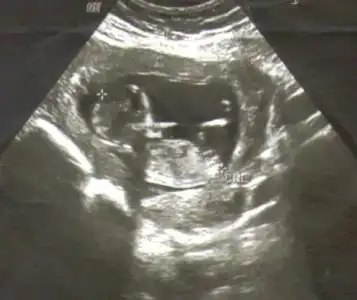

buda benim bebeğimin ultrason görüntüsü

henüz 11 +3 haftalık resmine çıplak gözle bakınca popo kısmında bir çıkıntı görülüyor fakat resmi tarayıp yükledim ama pek bir şey anlaşılmıyor galiba

acaca görebildiğiniz kadar yorum yapabilir misiniz Eki Görüntüle 806765 Eki Görüntüle 806765

Dikkatli baktım canım sanin çıkıntın paralel KIZ .. Gönlündeki olsun